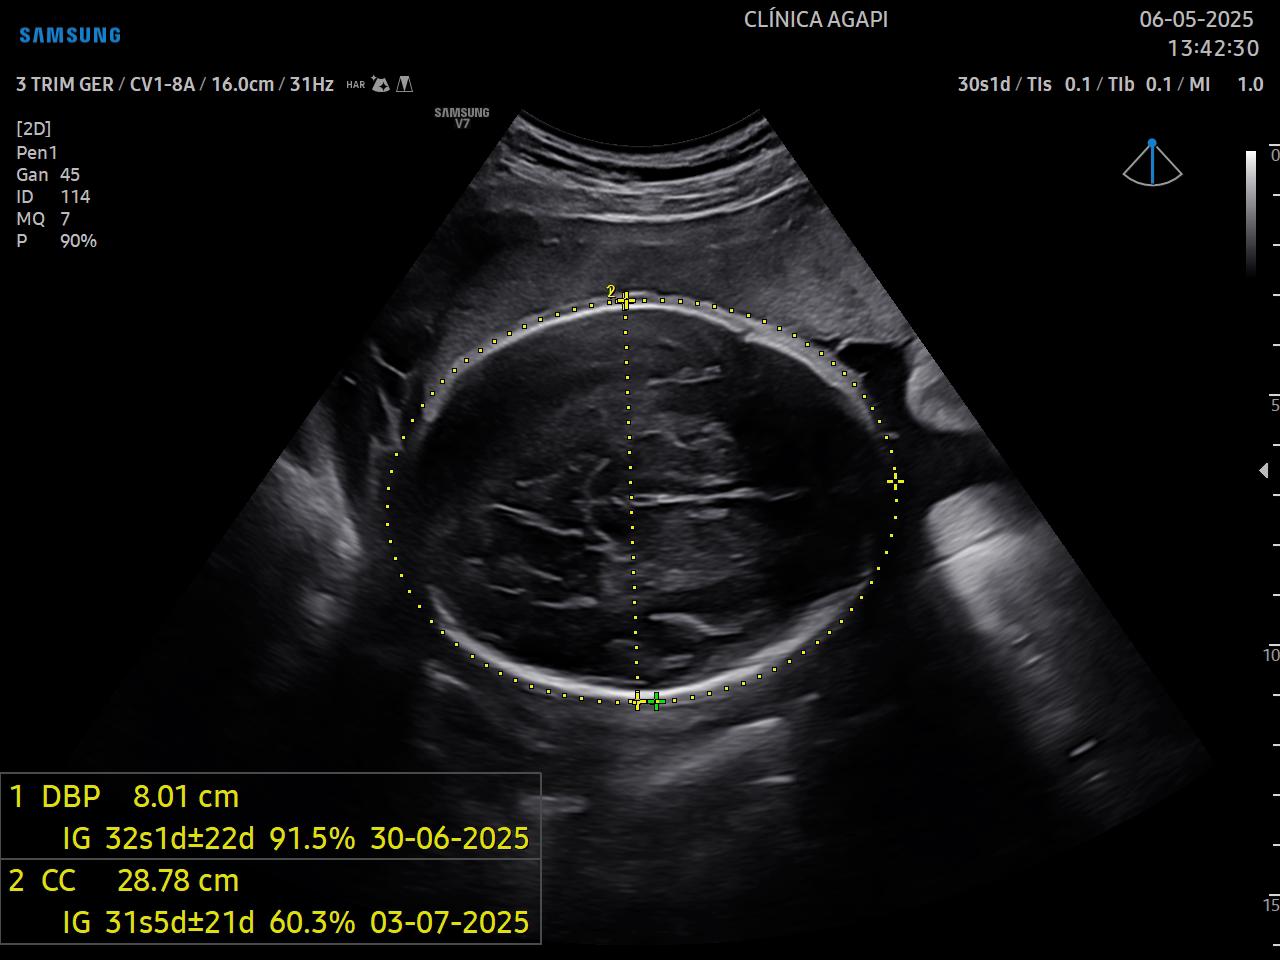

Exame realizado geralmente no 3º trimestre, avalia o crescimento e bem-estar fetal.

O doppler materno inclui a avaliação das artérias uterinas e o doppler fetal: artéria umbilical, artéria cerebral média, relação cérebro-placentária e quando necessário, ducto venoso.